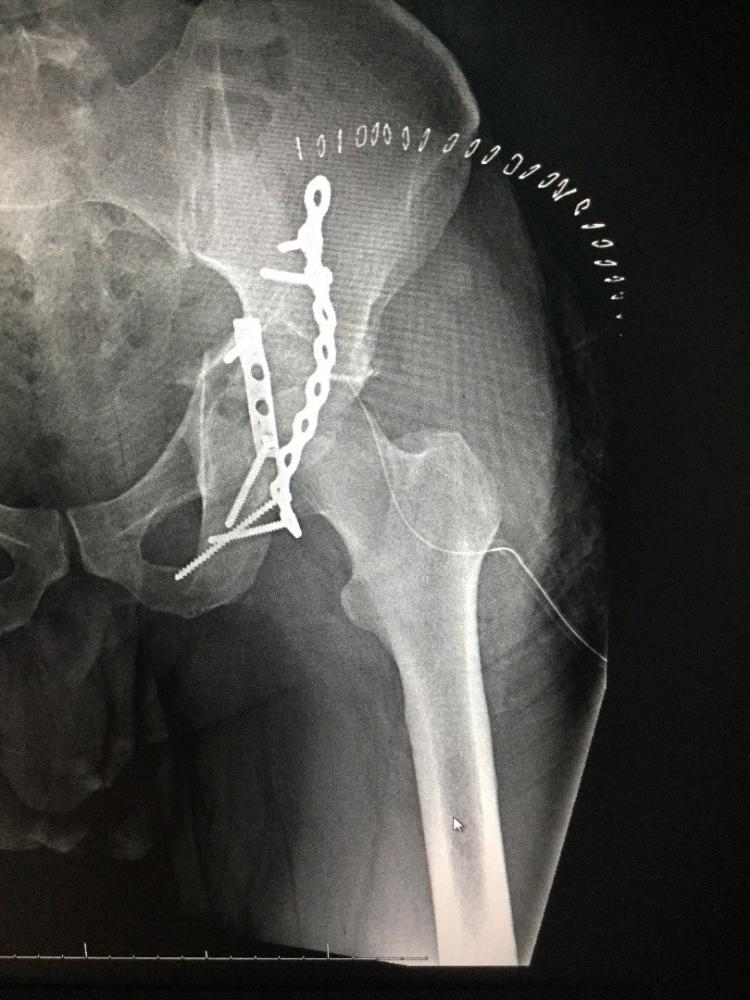

استقبل قسم الطوارئ بمستشفى القريات العام مواطن يبلغ من العمر 35 عاماً، أصيب في حادث مروري نتج عنه كسر مفتت بعظمة الفنجان (الجوف الحقي) للورك الأيسر.

واوضحت صحة القريات أن المريض وصل إلى المستشفى محولاً من أحد المستشفيات، وتم استقباله تحت إشراف استشاري جراحة العظام بالمستشفى، وبعد إجراء الأشعة والفحوصات المخبرية اللازمة، أجريت له على الفور عملية جراحية تكللت بالنجاح، تم خلالها تثبيت الكسر بشريحتين إعادة بناء مع البراغي المناسبة، وإعادته لوضعه السليم وتثبيت الكسر كاملاً، ولم تظهر أي مضاعفات أو التهابات ولله الحمد.